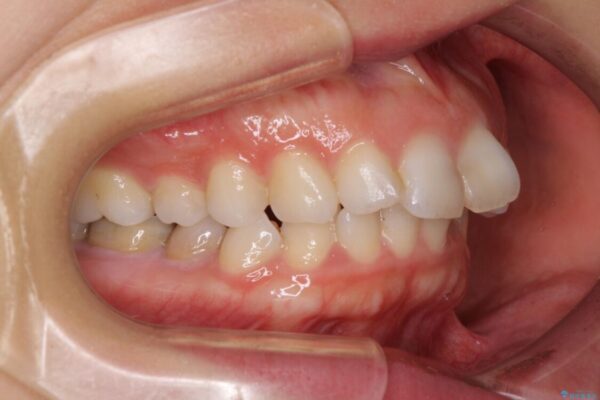

口元の閉じにくさと、奥歯の咬み合わせを気にして来院された患者様です。

左下の大臼歯2本が顕著に舌側に傾斜しているため、まずは奥歯の咬み合わせを改善をし、その後上下左右の第1小臼歯4本を抜歯することで口元を引っ込めながら整えることとしました。

治療前

• 【モニター】出っ歯と咬み合わせを改善 ワイヤー装置の抜歯矯正 治療前画像